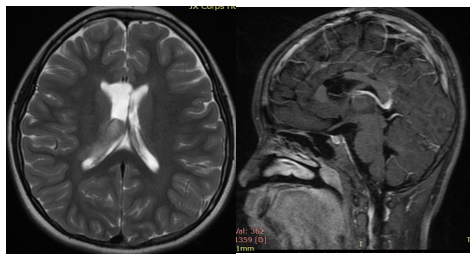

2、30多歲王女士,左側(cè)基底節(jié)區(qū)、腦干左側(cè)緣異常信號,對比三個月前的片子片少許增大,考慮低級別膠質(zhì)瘤可能性大。

Q:目前診斷是什么?教授的治療建議是什么?

A:從目前的新核磁改變來看,病變較前有所增大,并且根據(jù)目前的核磁,患者可能為彌漫性的膠質(zhì)瘤,雖然偏向于低級別,但病變組織是彌散生長在正常組織中的,故患者的情況無法給予治療性的切除手術(shù),但患者應(yīng)早日接受活檢手術(shù),早日明確診斷以便知道那個下一步的治療方案。由于患者病情的不同性,很遺憾不能給予病變組織的大范圍切除,但患者病變組織的生長特性,活檢手術(shù)需要在術(shù)中核磁指導(dǎo)下完成,以便能更準(zhǔn)確的取到病變部位的組織。建議盡早接受活檢做病理,早日確定診斷,早日開始治療。